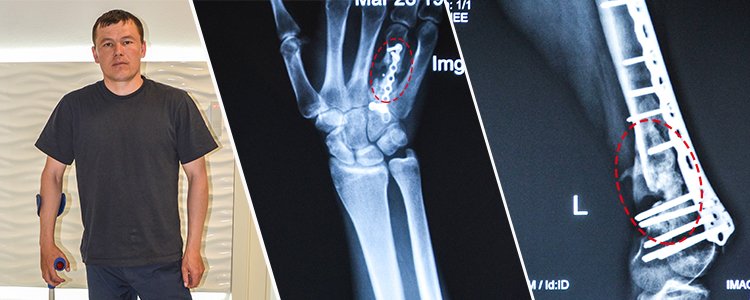

Першу допомогу надали у Кримському, потім доправили у Харківський військовий шпиталь, де на ногу встановили апарат Ілізарова, а у травні 2015 року у Київському центральному клінічному шпиталі зламану кістку зафіксували пластиною (виконали остеосинтез).

Сергій переніс вже 7 операцій на нозі, але за рік, який минув з часу останнього хірургічного втручання, кістки так і не зрослись. На даний момент, внаслідок порушеного кровообігу, м’язи ноги зсохлися і вкоротилися, від чого нога та пальці повністю не розгинаються.